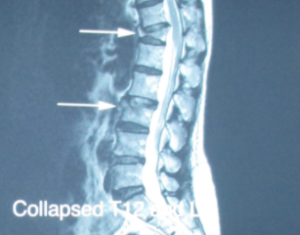

In April of this year, Ms. Guan fell again due to weakness in her feet. X-rays did not see any new fractures in the spine. However, the 12th section of the previous thoracic spine collapsed and bending forward. They gave her painkillers and anti-inflammatory drugs and ask her to go home and rest. After that, Ms. Guan found that the low back pain became more and more serious day by day. No matter sitting, walking, or standing, the low back pain could not be relieved. Even if the medicine was taken, the pain could not be relieved. The patient came to see the author in May. Because of her medical history and symptoms, it appeared that she fell due to weakness in both feet, and the patient herself suffered from osteoporosis, which caused her spine fracture after the fall. After detailed examination, it was decided to scan the cervical spine, thoracic spine and lumbar spine with MRI. It was found that the patient’s thoracic spine section 12 and lumbar spine section 3 were fractured. The thoracic spine section 12 was particularly severe, with compression, forward tilt, and compressing the cord (see Figure 1). The severe fracture made Ms. Guan’s low back pain worsened. The author referred the patient to a neurosurgeon for Vertebroplasty. After Ms. Guan completed this minor operation, the back pain that had troubled her for a long time almost disappeared.

The 12 thoracic vertebrae are particularly serious, with depression, forward tilt, and slight pressure to the central nervous system.